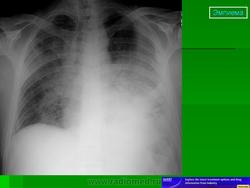

Иллюстрация 4. Субтотальное снижение прозрачности правого лёгочного поля с типичной косой верхней границей. Средостение смещено влево.

Иллюстрация 5. Феномен Ленка. Тотальное снижение прозрачности правого легочного поля.